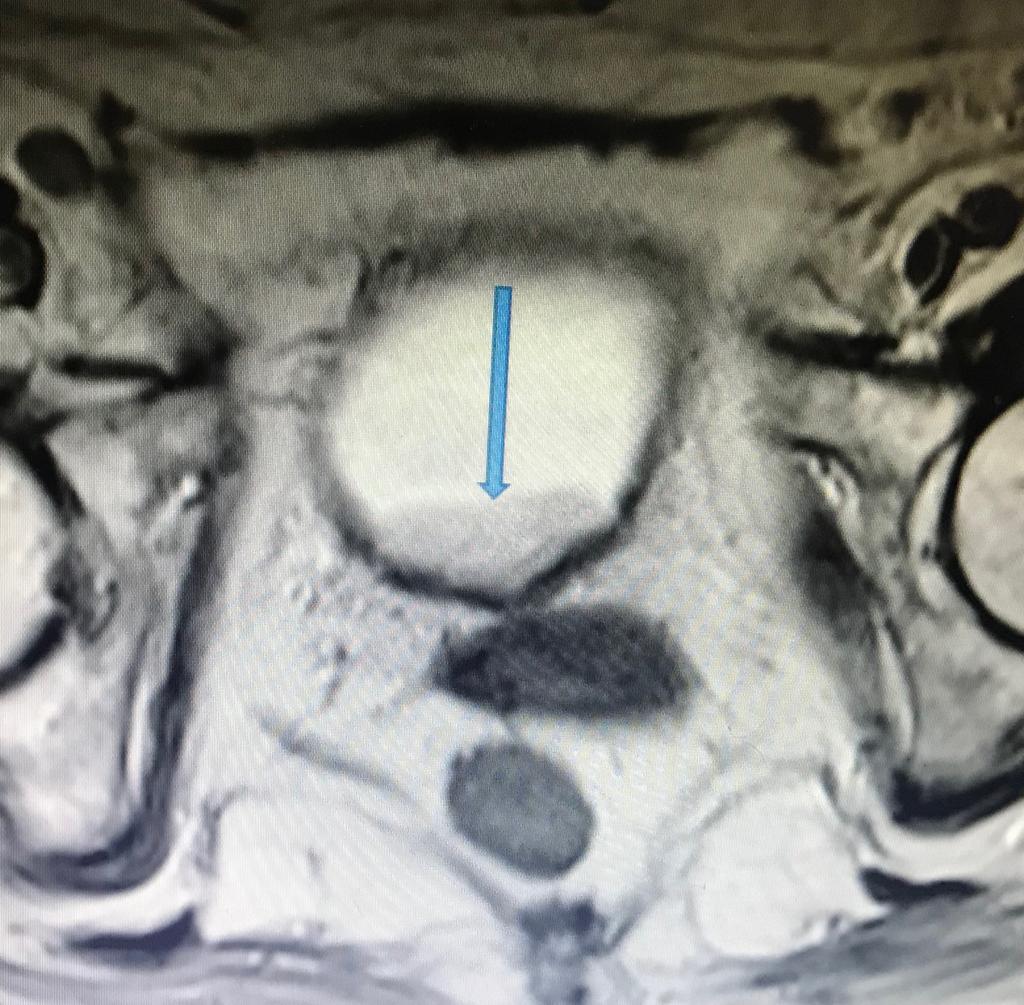

RM Biparamétrica de vejiga. (Cáncer de vejiga)

Femenina de 80 años, con prótesis en cadera derecha. Antecedente de IRC. No es posible realizar estudio de angiogénesis, por presentar TFG de 15ml/min y por consiguiente no administramos contraste endovenoso. Sin embargo, con las secuencias morfológicas y funcionales de la RM, es posible hacer el diagnóstico y el estudio de extensión de la lesión. ( T2 N0 M0. Estadio II). La Difusión -RM, nos permite determinar la celularidad tumoral y eventualmente monitorear la respuesta al tratamiento.